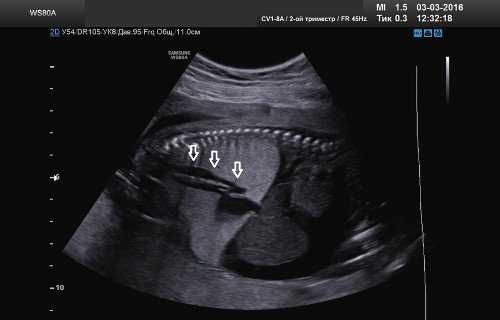

При тщательной оценке легочной ткани была выявлена расширенная на всем протяжении трахея (рис. 4) и расширенные бронхи (рис. 5).

Рис. 4. Парасагиттальный скан. Расширенная до уровня обструкции трахея.

Рис. 5. Поперечный скан. Расширенное бронхиальное дерево.